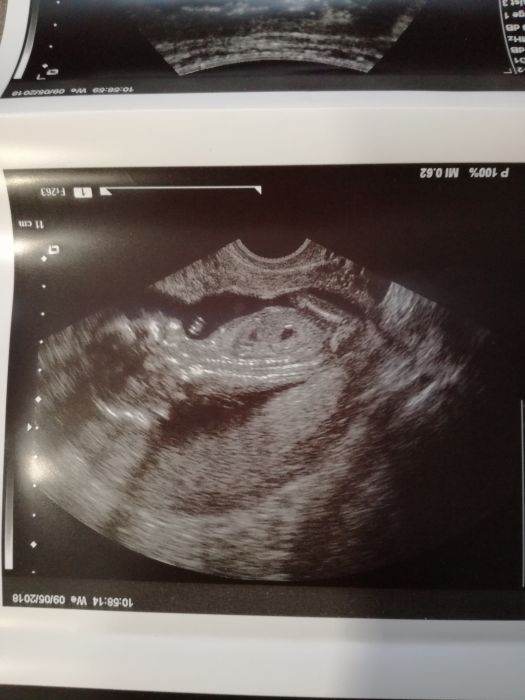

Ahoj holky, tak se hlásíme z kontroly. Prcek ok, vše v pořádku. Screening i krev taky, jen jsem dostala železo, ale to jsem měla i u první. Kolik měříme nevím, bude se měřit na velkém utz ve 20tt, kam se máme objednat. Jinak čekám kluka :) asi teda.. Dr. říkal, že mimčo je ještě malé, ale pindíka jsme viděli oba :D příště ještě potvrdíme. Hodím Vám sem fotky.

Můj chlapák :* :)